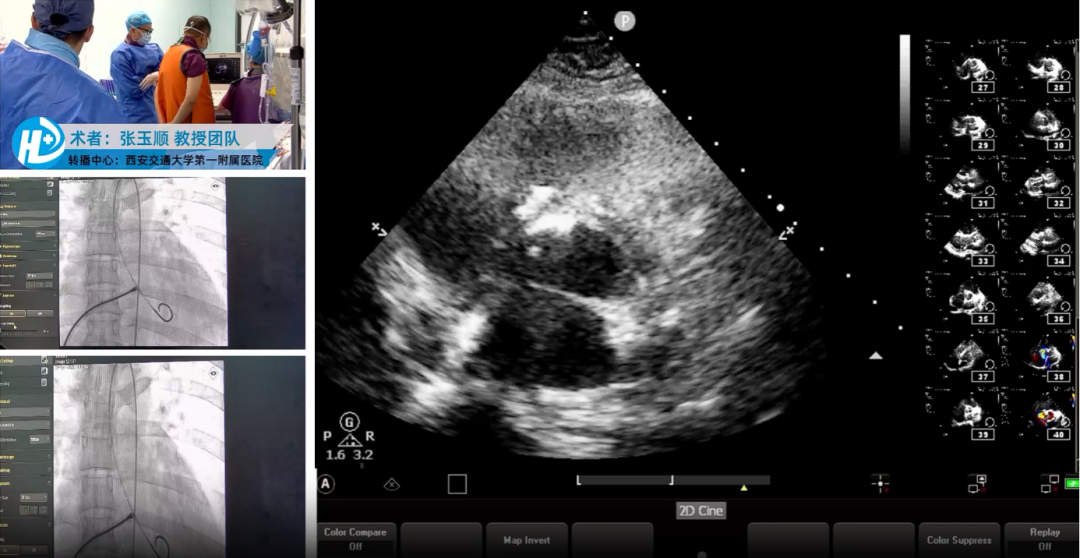

期间,张玉顺教授团队与秦永文教授团队完成了两例全降解封堵器植入术,成功为一例成人大型漏斗状膜部瘤室间隔缺损患者和一例成人先心病室间隔缺损修补术后残余漏患者植入全降解室缺封堵器,术后造影及经胸超声结果显示封堵器形态良好,对瓣膜无影响,无残余分流,封堵效果理想,两例手术均圆满完成。

结合手术演示,张玉顺教授还详细介绍了全降解封堵器经皮介入封堵的操作技巧及要领总结。强调了全降解封堵术“5S”操作法的重要性,一“贴”、二“扣”、三“锁”、四“剪”、五“撤”,并明确指出,术中超声下观察封堵器左盘展开后,需轻拉成型线,使封堵器左盘由球状拉成盘状,同时需做好封堵器锁定前的评估确认,再行剪断抽出成型线,保障封堵有效性及安全性。

手术转播环节,张玉顺教授团队、谢学刚教授与宋治远教授联袂完成了一例WATCHMAN FLX 封堵器植入术,术后造影及经胸超声结果显示封堵器形态良好,无残余分流,封堵效果理想。